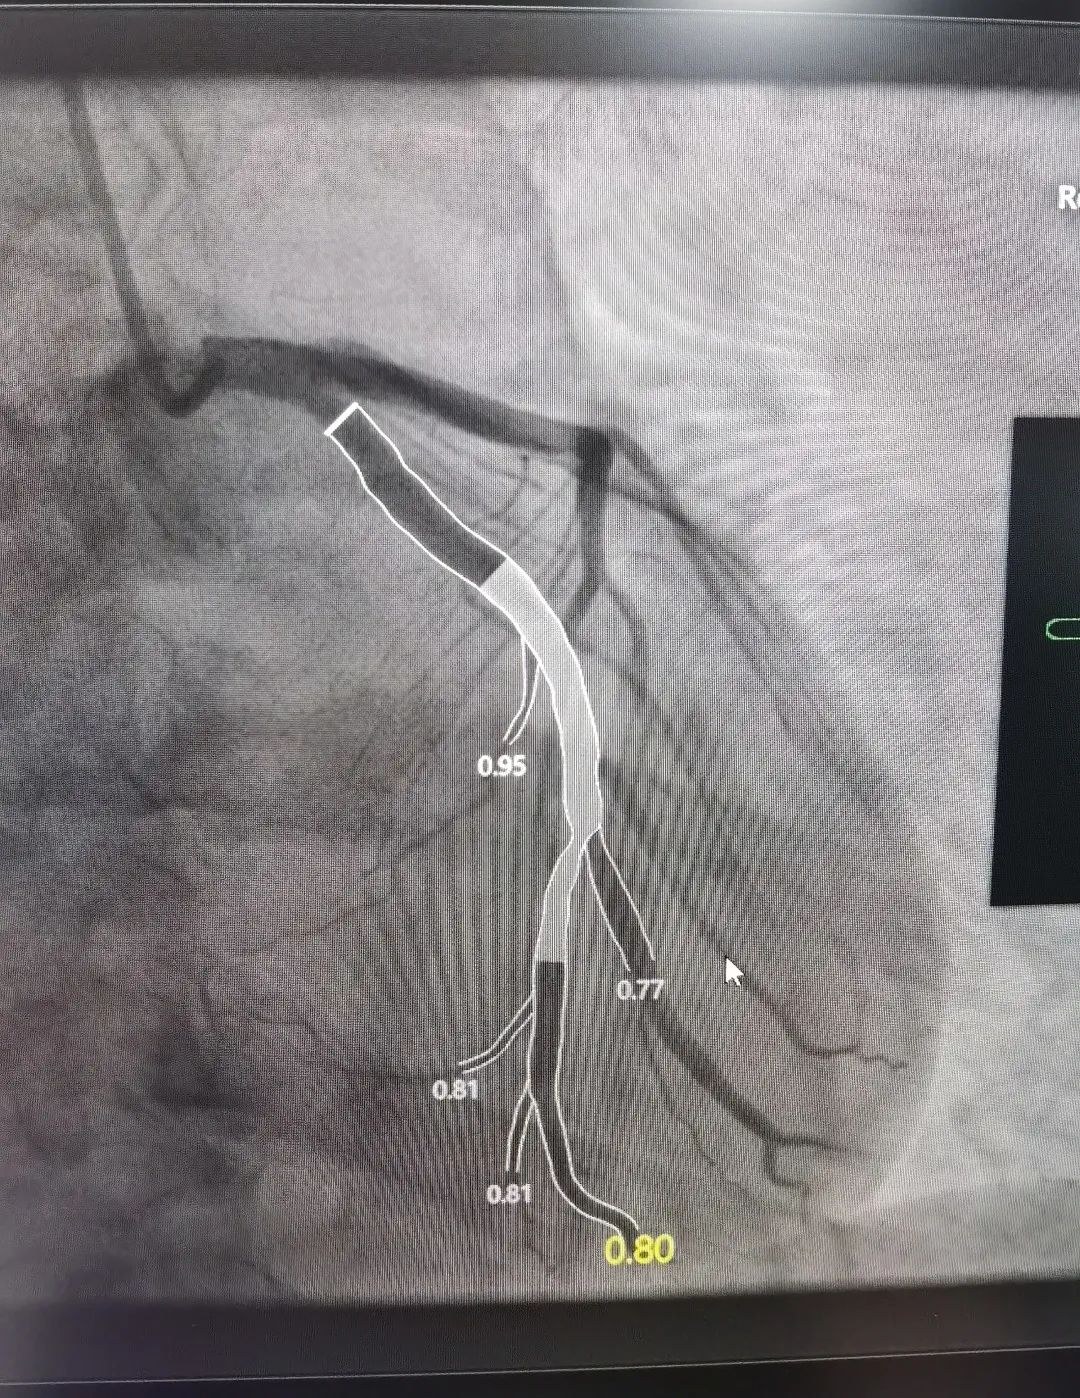

近日,一位 72 岁男性患者反复胸痛一年,加重一个月后来我院心内科治疗,心内科支部书记俞海峰主任医师为其实施在 QFR(定量血流分数)指导下的药物球囊治疗,真正做到精准治疗、绿色治疗。

术中的 QFR 依靠冠脉造影三维重建技术和血液动力学系统,并融入人工智能血流定量;精确分析狭窄冠脉血管的功能学指标,是无创、精确评估冠脉生理功能指标的「新标准」。

这位患者在 QFR 指导下对于分叉病变使用药物球囊治疗,避免了支架的植入对分叉另外一根血管的压迫,从术前和术后的 QFR 数值来看,手术收到了非常好的疗效。同时该患者不需要长期服用双联抗血小板药物,只需服用双联抗血小板药物一到三个月,因此对于特定病变和特定人群具有不少优势。

术前影像